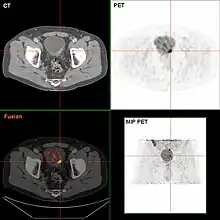

If invasive or high grade (includes carcinoma in situ) cancer is detected on TURBT, an MRI and/or CT scan of the abdomen and pelvis or urogram and CT chest should be conducted for disease staging and to look for cancer spread (metastasis).[56] Increase in alkaline phosphatase levels without evidence of liver disease should be evaluated for bone metastasis by a bone scan.[57] Although 18F-fluorodeoxyglucose (FDG)-positron emission tomography (PET)/CT has been explored as a viable method for staging, there is no consensus to support its role in routine clinical evaluations.[54]

Surveillance and response

Contrast enhanced CT is used to monitor lung, liver, and lymph node metastases. A bone scan is used to detect and monitor bone metastasis.[158] Treatment response is measured using the Response evaluation criteria in solid tumors (RECIST) into one of the following groups; response (complete or partial), stable disease and progressive disease.[159]